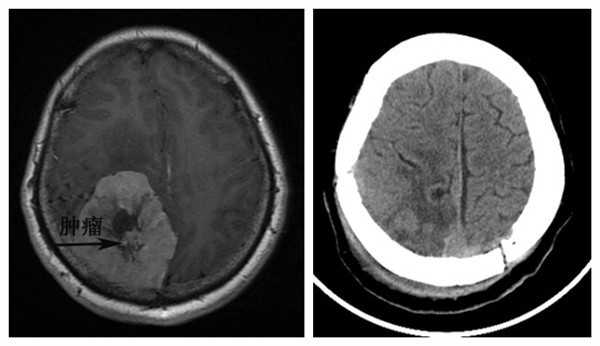

术前磁共振,提示右侧顶枕叶巨大肿瘤 术后CT,提示肿瘤已切除

病人已经在多年前出现了出现了头痛,视力下降,凸眼等许多症状,然而要等到肿瘤长到拳头样大小才来就医,我们也觉得十分惊讶。屈建强教授、周乐副教授、张熙主治医师接到病人后,为患者制定了周密的手术计划。首先为了精确定位肿瘤,我们术前应用神经导航来标记肿瘤的位置,然后根据肿瘤的位置来设计皮肤的切口;其次,术前预计手术中可能会出现大量出现,因此,术前提前准备了大量的血液,术中每一步操作都必须止血严密;另外,该肿瘤表面存在大量的血管,术中尽量保存正常的血管结构;最后,肿瘤的前方与脑功能区比邻,如果损伤到脑功能区,可能导致患者肢体感觉和运动障碍。因此,在手术操作中,严格按照脑组织与肿瘤的分界来操作,减少对脑组织的损伤。经过医护人员9个多小时的紧张的忙碌,手术获得了圆满的成功。手术后文女士恢复非常顺利,头痛,恶心等症状消失了,双眼视力明显好转,眼球突出也基本恢复正常了,并且没有出现任何的肢体功能障碍。患者和家属感到非常满意,对我们说:“真是太感谢你们了,是你们医护人员给了我们家第二次生命”。我们也觉得十分欣慰,患者的康复就是对我们医护人员最大的肯定。